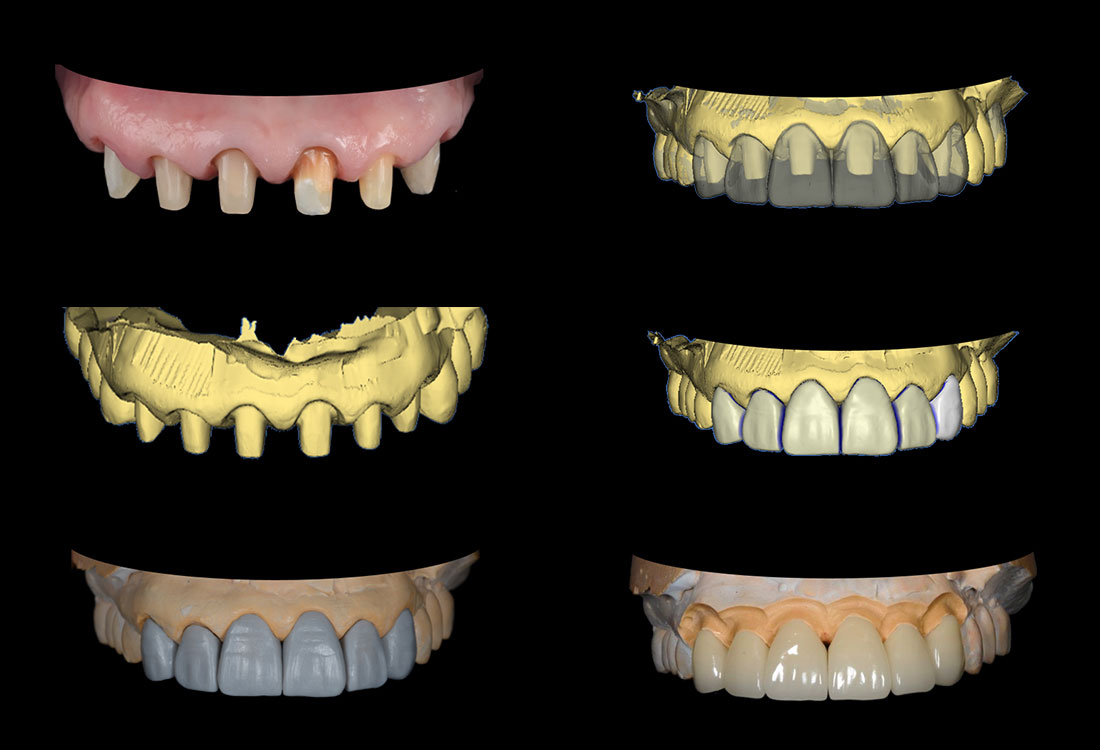

治療症例 Case3

Treatment cases

ご相談内容

- 上の左右2番目の歯と尖っている前歯が気になる

- 歯の形を治したい

- 歯の色をきれいにしたい

ホワイトニングで全体的に白くした後、その色に合わせて被せ物を作っていきます。

治療内容

模型を作成して最終的な形を模索します。

ファイバーコアで神経のない歯に土台を作ります。

ファイバーコアは保険治療で使われるメタルコアと異なり白く、被せ物が透けて黒く見えません。

土台になる歯の形を整えて最終的な形の模型を作ります。

治療後

白く明るい口元になりました。